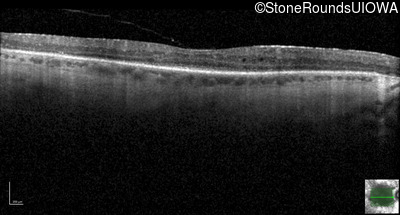

Optical Coherence Tomography - Right - 20/32 -2

Exemplar / OCT Stack

OCT Stack